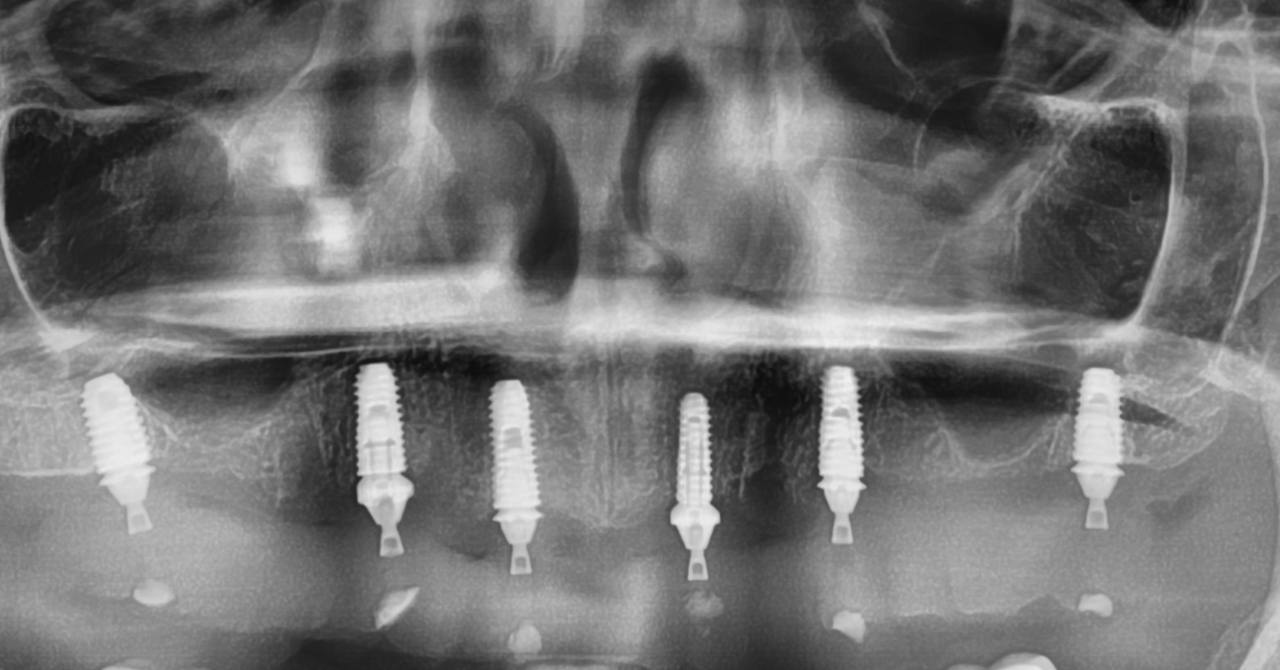

Имплантация верхней и нижней челюстей на 6 имплантах